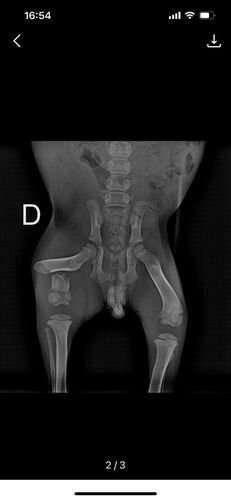

Ela e a irmã foram abandonadas na rua e um carro atropelou apenas ela, onde teve fratura total no fêmur.

(segue imagens do raio x)